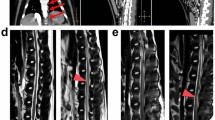

In the surgical treatment of an aortic aneurysm, disruption of the blood supply to the spinal cord, resulting in paraplegia and anaesthesia below the level of involvement, is a dreaded complication. Occasionally, when an aortic aneurysm compresses a major vessel that supplies the anterior spinal artery, spinal cord ischaemia and paraplegia can occur before surgery. In the case presented here, however, preoperative paraplegia appears to have resulted from direct spinal destruction by an infected aortic aneurysm that was originally diagnosed as a spinal abscess. The patient underwent operative repair, but her aorta was so friable that the sutures would not hold. Despite repeat surgery, her condition rapidly proved fatal. This case shows that, in patients with a suspected spinal abscess, computer tomographic scanning and angiography should be performed to confirm the diagnosis and to rule out other pathological conditions. An accurate pre-operative diagnosis will permit adequate operative planning and prevent catastrophic results.

Rubio, P., Nelson, P. Mycotic thoracic aortic aneurysm producing vertebral body destruction and paraplegia: case report. Spinal Cord 27, 406–409 (1989). https://doi.org/10.1038/sc.1989.64